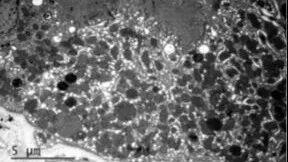

结合肾穿刺标本的电镜复核,发现足细胞及肾小管上皮细胞内可见少量形态异常的线粒体,最终明确诊断为CoQ8B肾病。

CoQ8B肾病是一种与线粒体功能障碍相关的遗传性肾病,可表现为蛋白尿、FSGS样病理改变及肾功能进行性下降,且并非仅发生于儿童,成人同样可能发病。